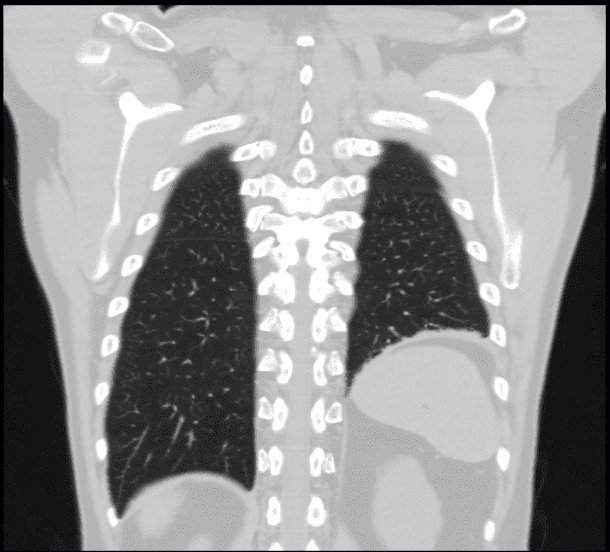

Corrección de la parálisis diafragmática

Se realiza plicatura del diafragma paralizado por causa conocida o idiopática.